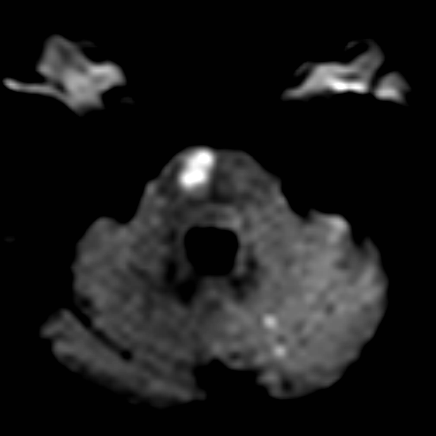

相逢就是缘,有求必全力以赴。立即进行全面评估,CTA和MRI发现颅内多发脑梗塞,脑干为重,双侧椎动脉颅内段基本看不到了,而进一步的DSA造影更为糟糕,左侧椎动脉的颅内颅外段直接全程完全闭塞,右侧颅外剩下一个小尾巴在血液中摇摇欲坠……,诺大的后循环仅仅靠纤细的后交通动脉从前循环借点血液过来,勉强续命,仅仅靠这点前循环的救急,可谓“杯水车薪”,不是“长久之计”,于是决定开通右侧闭塞的椎动脉(颅内+颅外,主要集中在V3+V4段)。